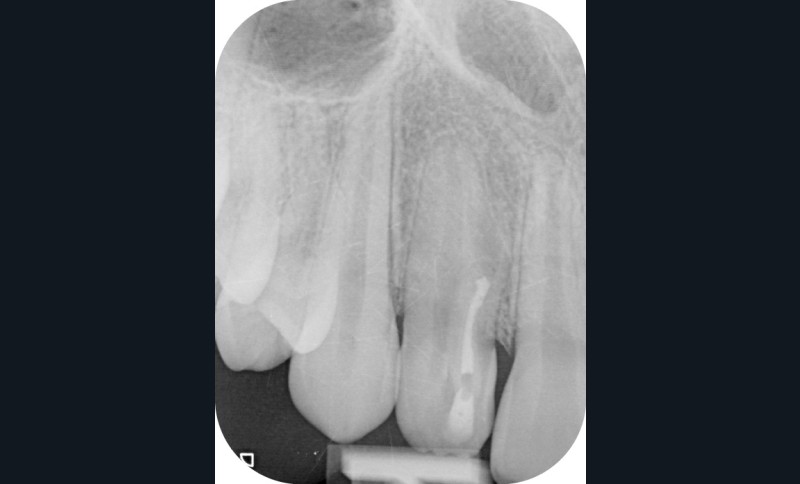

La patiente, âgée de 12 ans, s’est présentée à ma consultation avec une demande du chirurgien de réaliser le traitement endodontique de la 12 avant le curetage sous anesthésie générale. La radiographie périapicale préopératoire a mis en évidence une anatomie complexe. Les tests préopératoires ont montré un sondage parodontal sain, une percussion positive et un test au froid positif. La patiente présentait également une fistule vestibulaire active. Le Cone Beam a mis en évidence la présence d’une dens in dente et d’une lésion imposante ainsi qu’une palatoversion importante de la racine de la 12. La lésion est-elle responsable de ce mouvement dentaire ? (fig. 1, 2 et 3).

Le test au froid et la position de la lésion m’ont permis de prendre ma décision thérapeutique. En effet, la lésion située uniquement sur la face vestibulaire de la dent en regard de l’apex du canal de la dens in dente et la persistance d’un test au froid positif à travers chacune des séances de soins m’ont permis de m’assurer que la dent principale était bel et bien vivante.